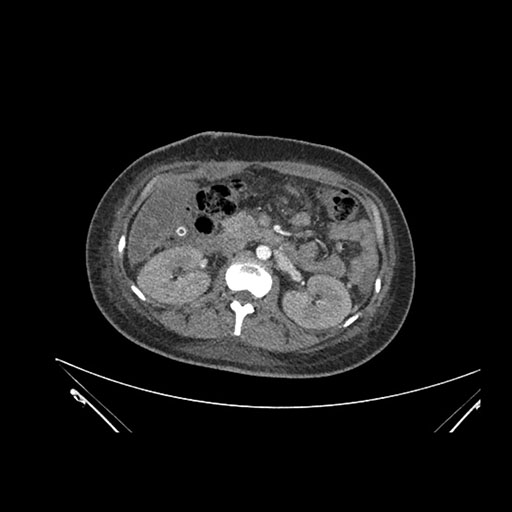

Look through the patient's CT scan to identify any areas of concern for the necessary procedure.

Axial Arterial